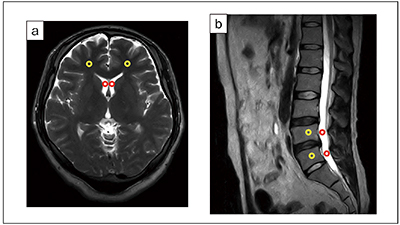

IP-Reconを使用することで画像のコントラストは変化するのでしょうか。健常ボランティアの画像からコントラスト比を測定して検証しました。コントラスト比は,画像上に設定した2か所の関心領域(ROI)における画素値の平均値から算出しました(図3)。撮像条件は頭部,腰椎のT2WI,T1WIを想定し,IP-Reconを使用していない画像とノイズ除去強度を変えた画像を取得して,コントラスト比を算出しました(図4)。

コントラスト比= ¦S1−S2¦/(S1+S2)

S1はROI1(図3 ○)における画素値の平均値,S2はROI2(図3 ○)における画素値の平均値をそれぞれ示しています。

頭部T2WI(図4 a)を例に挙げると,コントラスト比はIP-Recon Off:0.58,Light:0.57,Medium:0.59,Heavy:0.58となり,ノイズ除去強度によらず同程度の値となりました。また,ほかの撮像条件でも同様の傾向でした。このことから,今回評価した撮像条件において,IP-Reconを使用しても画像のコントラストは変化せず,ノイズ除去強度を変えてもコントラストに影響はないことがわかります。

図3 コントラスト比測定におけるROIの設定

a:頭部T2WI. 白質(○)と側脳室(○)にROIを設定

b:腰椎T2WI. 椎体(○)と脳脊髄液(○)にROIを設定